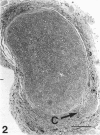

The morphological changes were examined proximal and distal to crush and transection injuries of the lingual/chorda tympani nerve. Under general anaesthesia the nerve was transected unilaterally in 6 adult cats and crushed with watchmakers forceps in 6 others. After 12 wk, again under general anaesthesia, the injured and contralateral (control) nerves were removed, fixed and embedded for histological examination. Sections were cut from sites proximal and distal to the injury and from a site equivalent to that of the injury on the control side. Using systematic randomised sampling techniques the number of nonmyelinated axons and the number and size of myelinated axons in each nerve at each location was estimated. In addition, the mean number of nonmyelinated axons in each Schwann cell unit was determined. The only significant difference between control and injured nerves proximal to either injury was a reduction in the number of myelinated axons in the chorda tympani after transection, and an increase in their mean size. This indicates a selective loss of smaller fibres and is consistent with the poor recovery of gustatory and thermosensitive fibres previously reported (Robinson, 1989). Distal to both types of injury there was an increase in the number of fascicles. The mean number of myelinated axons was reduced distal to a crush injury but unchanged distal to transection. The number of nonmyelinated axons distal to a transection injury was 5 times control counts and after a crush injury double. These findings suggest that sprouting persists 12 wk after both injuries but is much greater after transection.